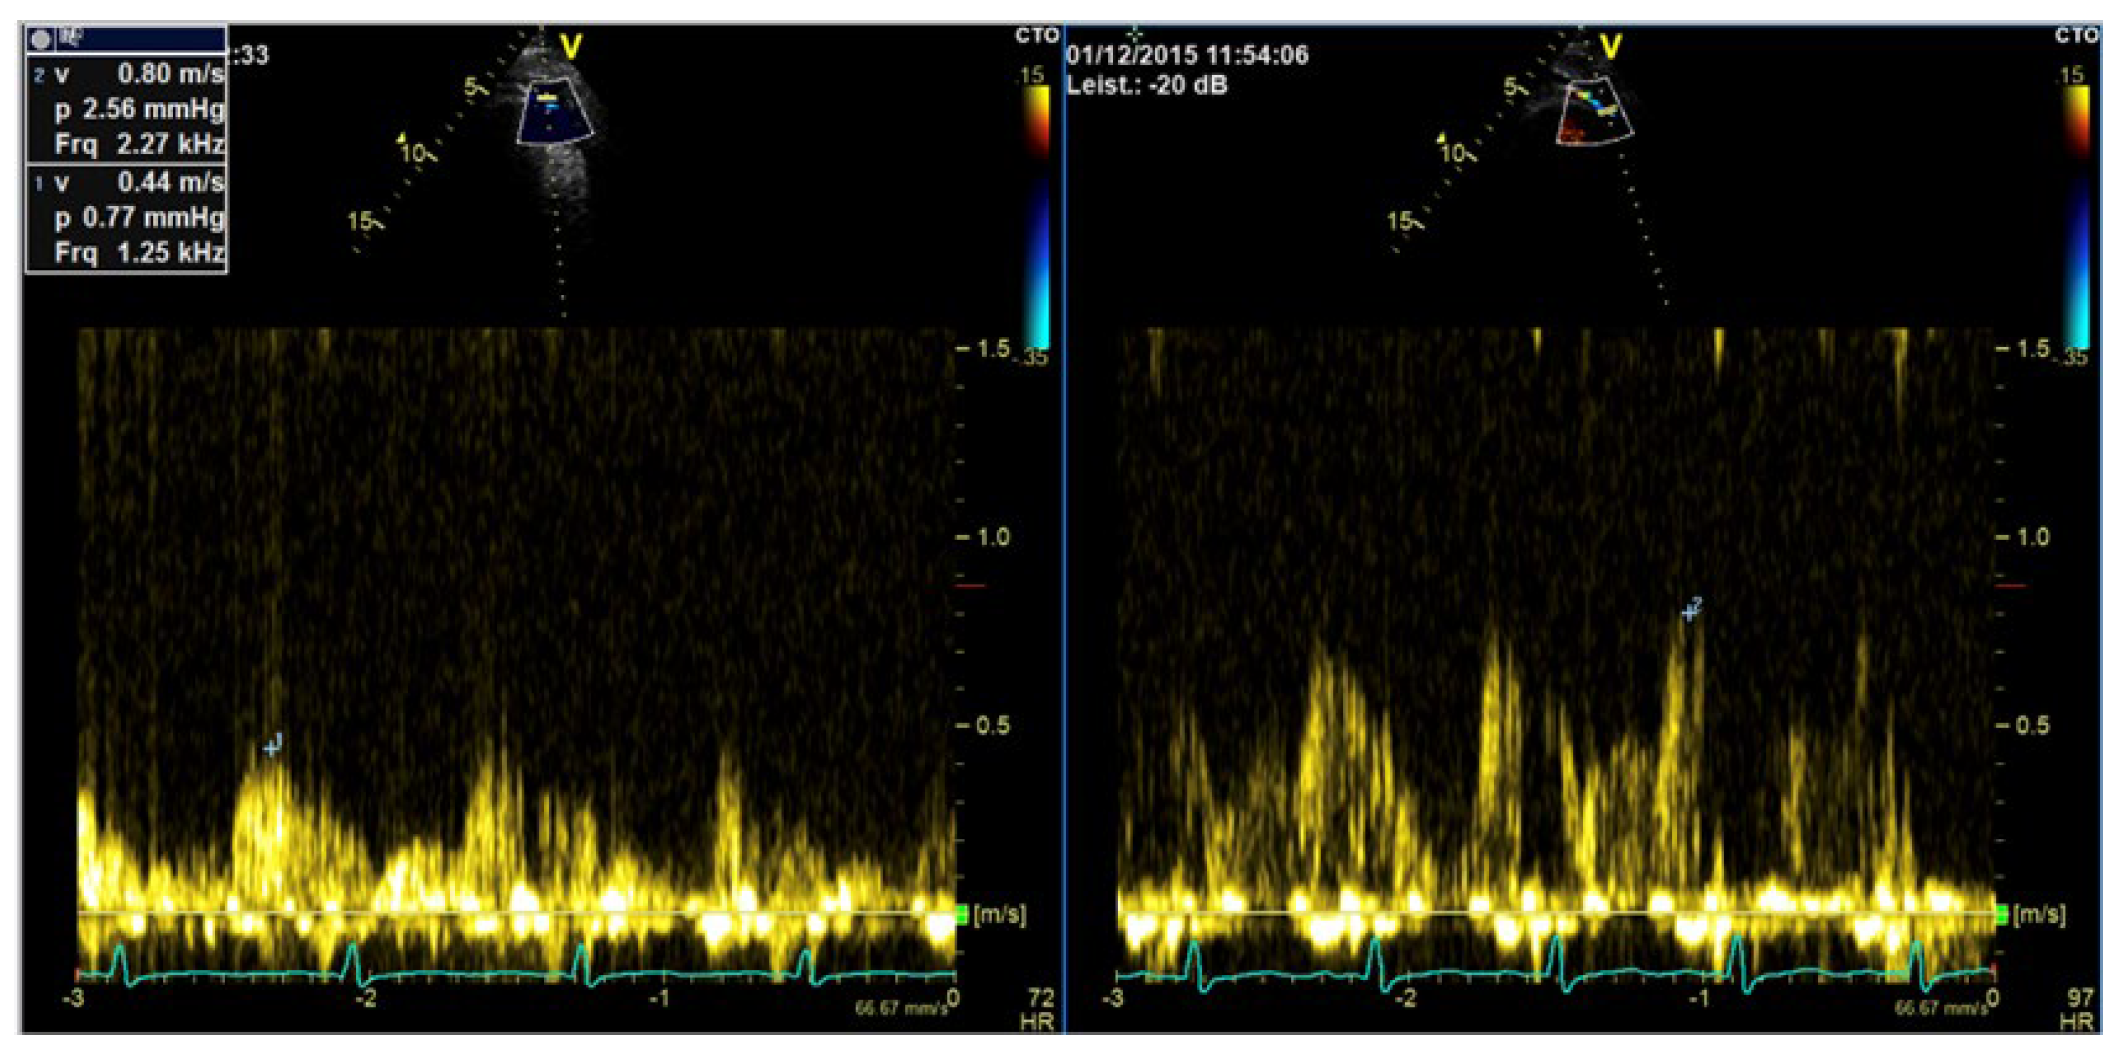

| Flow assessment in epicardial coronary arteries (Color and PW Doppler) |

| Aortic stenosis (CW Doppler) |

| Pulmonary venous flow (PW Doppler) mitral regurgitation |

| Tricuspid regurgitation (CW Doppler) for measurement of PA pressure * |

| Imaging method | CW Doppler for aortic stenosis/tricuspid regurgitation PW-Doppler: for pulmonary–venous flow |

| Imaging planes | Same as for non-contrast Doppler imaging, the enhanced color Doppler signals facilitate the alignment of the cursor for spectral Doppler measurements |

| Contrast application | Bolus injection, the recordings can be performed during the washout after recordings for assessment of LV function |

| Typical findings | Intensive Doppler spectra Consider reduction in gain or power. |

| Alternative imaging | TEE, cardiac MRI |